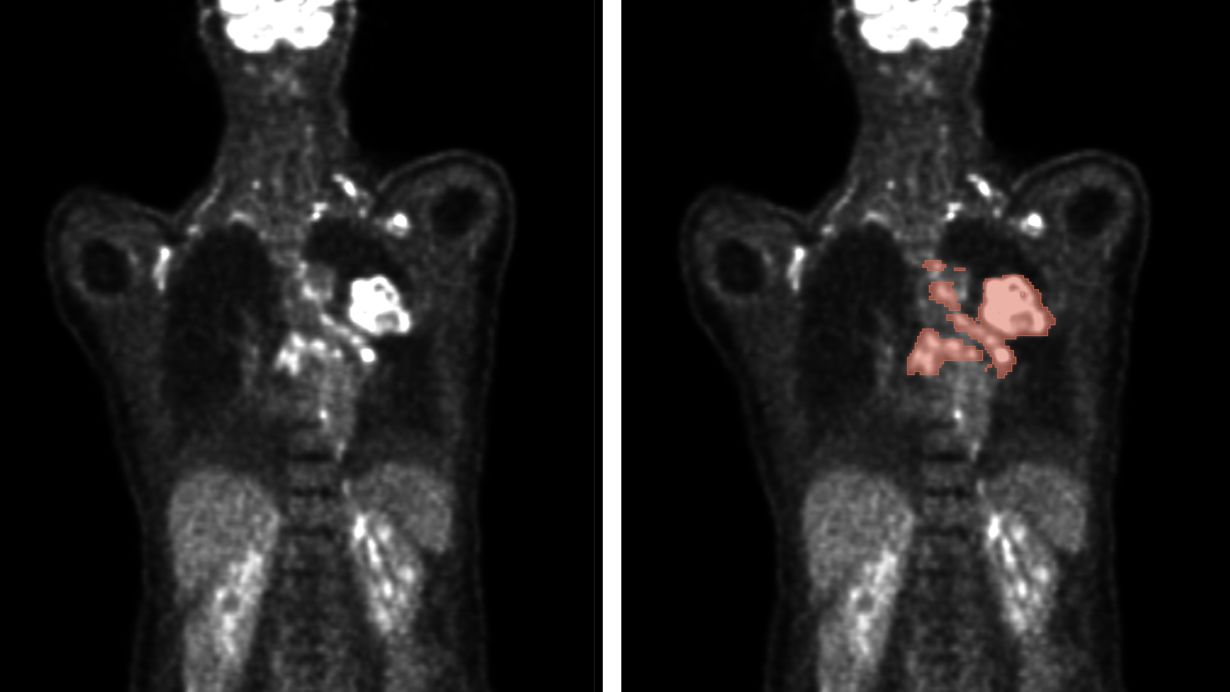

Automatische Verfahren ermöglichen die Analyse von PET/CT-Scans (links) zur präzisen Vorhersage von Tumorlage und -größe (rechts) für eine verbesserte Diagnose und Therapieplanung

Automatische Verfahren ermöglichen die Analyse von PET/CT-Scans (links) zur präzisen Vorhersage von Tumorlage und -größe (rechts). (Abb.: Gatidis S/Kuestner T., ausführl. Bildunterschrift und Quelle am Textende)

Ausführliche Bildunterschrift: Automatische Verfahren ermöglichen die Analyse von PET/CT-Scans (links) zur präzisen Vorhersage von Tumorlage und -größe (rechts) für eine verbesserte Diagnose und Therapieplanung. (Abbildung: Gatidis S, Kuestner T. (2022) A whole-body FDG-PET/CT dataset with manually annotated tumor lesions (FDG-PET-CT-Lesions) [Dataset]. The Cancer Imaging Archive. DOI: 10.7937/gkr0-xv29)